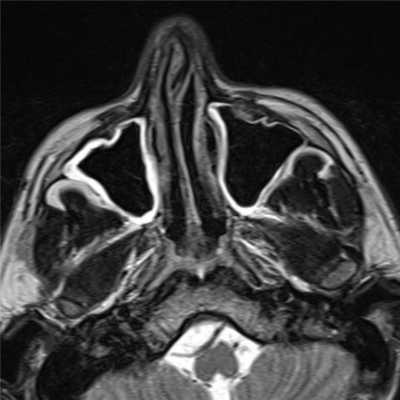

MPT

• В большинстве случаев мукоцеле дает гипоинтенсивный сигнал на Т1 и гиперинтенсивный на Т2в-изображениях.

В ряде случаев пазуха выглядит расширенной, но с сохраненной воздушностью, она гипоинтенсивна как на Т1, так и на Т2.

Магнитно-резонансная томография

Интенсивность МР сигнала зависит от соотношения количества воды, слизи и белков 2:

- T1

- высокое содержание воды: низкая интенсивность сигнала (чаще всего)

- высокое содержание белков: высокая интенсивность сигнала

- высокое содержание воды: высокая интенсивность сигнала (чаще всего)

- высокое содержание белков: низкая интенсивность сигнала

NB: присоединение грибковой инфекции ведет к снижению сигнала на T1 и T2 взвешенных изображениях, симулируя нормально аэрированные синусы [4].